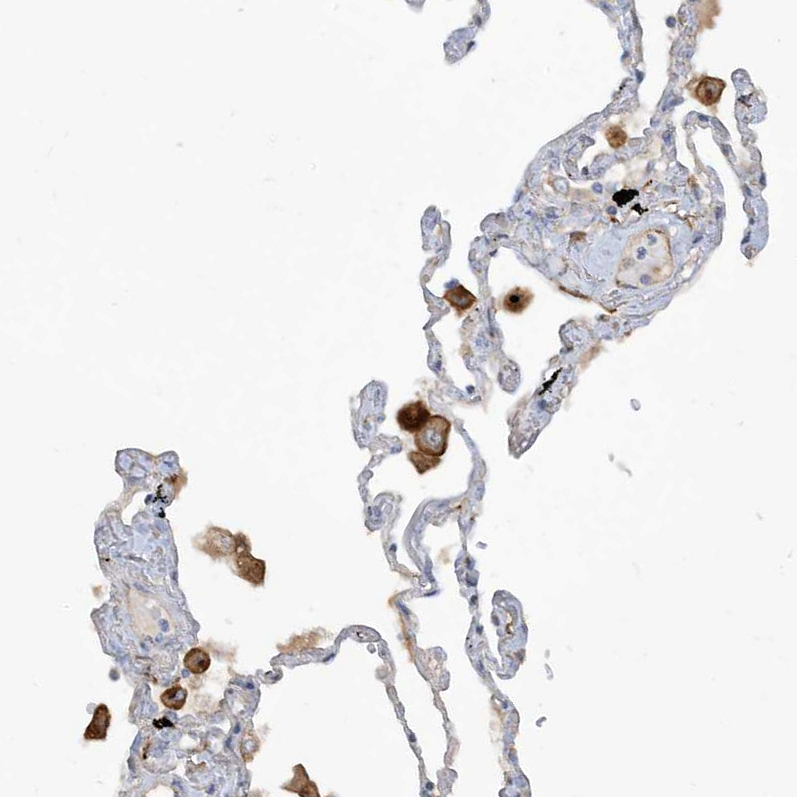

Immunohistochemical staining of human bone marrow shows moderate membranous positivity in hematopoietic cells.